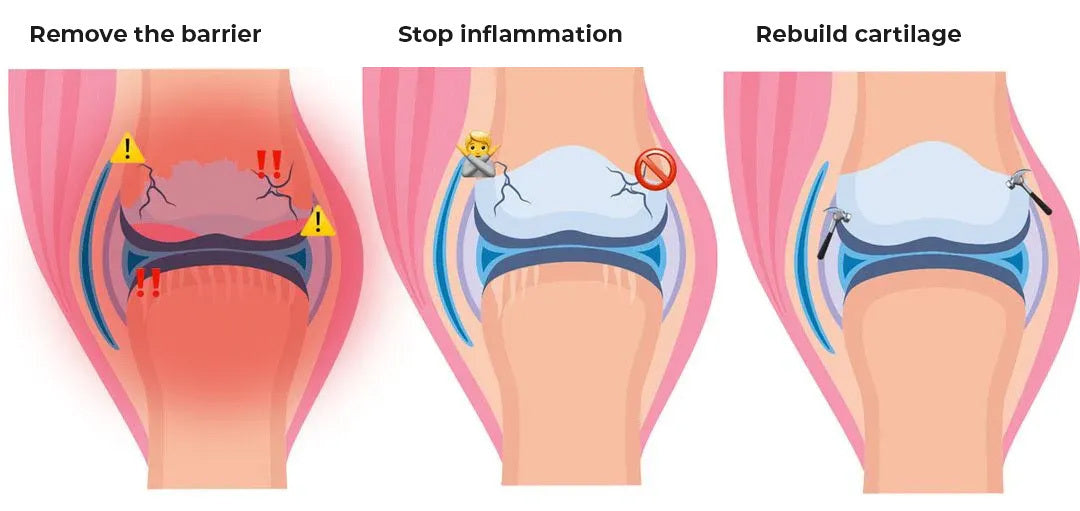

These are the three crucial steps:

Stop Inflammation – The Fire in Your Joints

Hormonal fluctuations cause chronic inflammation, which literally attacks the cartilage. The natural active ingredient Boswellia and Turmeric in the form of boswellic acid has a targeted anti-inflammatory effect and protects your cartilage instead of damaging it like many painkillers.

Without anti-inflammatory measures, your body cannot break through the waste barrier and all other measures are ineffective.

Breaking the Waste Barrier – The Key to Healing

During menopause, waste builds up in the joints as blood and lymph flow is disrupted. OPC (grape seed extract) improves blood flow, breaks down this barrier, and brings fresh nutrients to where they are needed. It also removes inflammatory waste products and clears the way for important nutrients.

Cartilage Repair – The Basis for Mobility

Your cartilage can only repair itself if it gets the right building blocks. Bamboo extract provides these essential substances and activates the body's cartilage production.

But only when the inflammation has stopped and the barriers are broken can the cartilage be rebuilt. This is the key to healthy, resilient joints in the long term.

These three steps together ensure that the joint detox method is unique.

It is the first approach that addresses the root causes of your problems – exactly where conventional solutions fail.